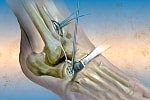

滑膜切除術

滑膜切除術は一般に、関節リウマチがステージ1~2の段階で、まだ軟骨が十分残っている早期に行われる手術です。関節破壊が進んで、軟骨がすでになくなっているようなケースでは行えません。

●内視鏡下の切除術が主流

滑膜切除術は、かつては関節を大きく切り開いて滑脱をとり除く外科的切除術が行われていましたが、現在は内視鏡下での手術が主流になっています。

皮膚に小さな孔をあけ、内視鏡(関節鏡)を挿入して、モニターに映し出された画像を見ながら行う手術です。切開する部分が小さいため、患者さんへの負担も少なく、回復が早いというメリットがあります。

●行われる部位

ひざ関節への滑膜切除術は治療効果があり、よく行われます。ただし医師によっては、ひざなど大きな関節には不向きであるとする意見もあります。そのほか、手首、肩、ひじ、足首などに行われます。